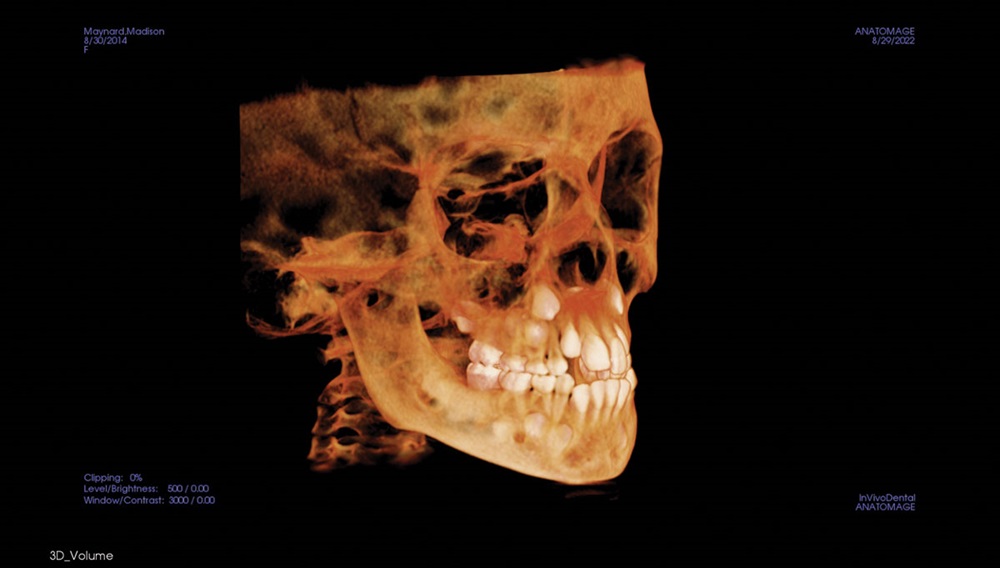

The TMJ tab in the software (Fig. 14)

is used to identify gross abnormalities and

assess the symmetrical positioning of the

condyles in the fossa, while the Volume tab

(Fig. 15), used to assess crowding, impaction

and relative jaw relationships, gets the most

reaction from the parents and children.

Fig. 14

Fig. 15